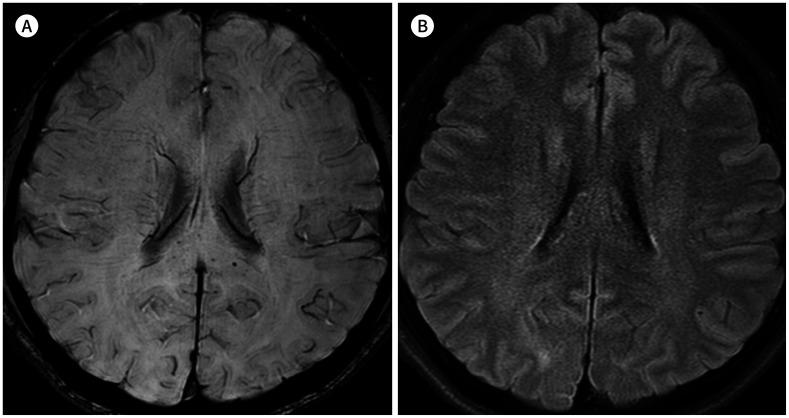

Microbleeds in the Corpus Callosum in Anoxic Brain Injury.

This study was performed to evaluate the relationship between callosal microbleeds and anoxic brain injury.

The prevalence of cerebral microbleeds in the patient group was 29.6%, which was significantly higher than that in the control group at 3.7% ( = 0.012). All cerebral microbleeds in the patient group were in the corpus callosum. Compared with the callosal microbleed-absent group, the callosal microbleed-present group showed a tendency of good prognosis (6/8 vs. 11/19), fewer typical MRI findings of anoxic brain injury (2/8 vs. 10/19), and more cardiopulmonary resuscitation (6/8 vs. 12/19), although these differences did not reach statistical significance ( = 0.35, = 0.19, and = 0.45, respectively).

Callosal microbleeds may be an adjunctive MRI marker for anoxic brain injury.